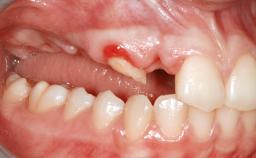

Shell Technique for Horizontal and Vertical Maxillary Bone Augmentation in a Partially Edentulous Patient with Aggressive Periodontal Disease

A 46-year-old woman was referred for treatment whose main complaints were mobility of her fixed partial dentures (right maxilla and left mandible) and periodontal bleeding during function. She also reported having taken systemic antibiotics to treat recurrent swelling in the area of the upper left molars. The patient had not seen a dentist for at least 2 years. She did not smoke and had no history of major systemic disease other than two minor orthopedic procedures some years back. The first-visit examination revealed poor plaque control, tooth mobility, periodontal disease, and a residual dentition widely associated with deep periodontal pockets.

Soft Tissue Anatomy Intact Defective

Bone Volume Horizontally and vertically sufficient Horizontally deficient Deficient vertically or deficient vertically AND horizontally